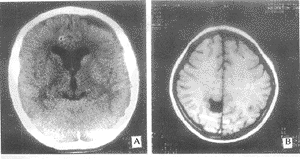

图3 分别为左侧额区蛛网膜囊肿、右顶部纵裂旁蛛网膜囊肿,术中均发现病灶边缘有癫痫波,病理提示胶质增生

1例蛛网膜囊肿位于右颞窝病人(图1)、1例位于环池病人(图2)及1例位于颞角病人脑电图提示有癫痫波,以颞叶癫痫做前颞叶切除术,术中见海马结构及部分颞叶皮层有异常波或癫痫波,病理均提示颞叶皮层和海马结构胶质增生。1例额部(图3A)及1例顶区蛛网膜囊肿(图3B)病人做囊肿切除术,术中见病灶周围异常波。所有手术病人术后短期随访4例无癫痫发作,1例发作减少。

颞叶由于其解剖和组织结构的特殊性,对缺血缺氧和损伤极为敏感,认为海马区特别容易受损而形成致痫灶;海马结构主要传入纤维来自内嗅区,也来自扣带回和隔核等处,而穹隆是其主要传出纤维,可见海马结构与大脑其它部位有广泛的联系,所以颞叶是癫痫的好发部位,鉴于上述电生理和解剖病理特点,可以解释为什么本组颞区蛛网膜囊肿病人引起癫痫发作的发病率较其它部位的囊肿高,图3、4所示环池囊肿长期压迫海马结构导致后者硬化可能是引起癫痫发作的原因之一。